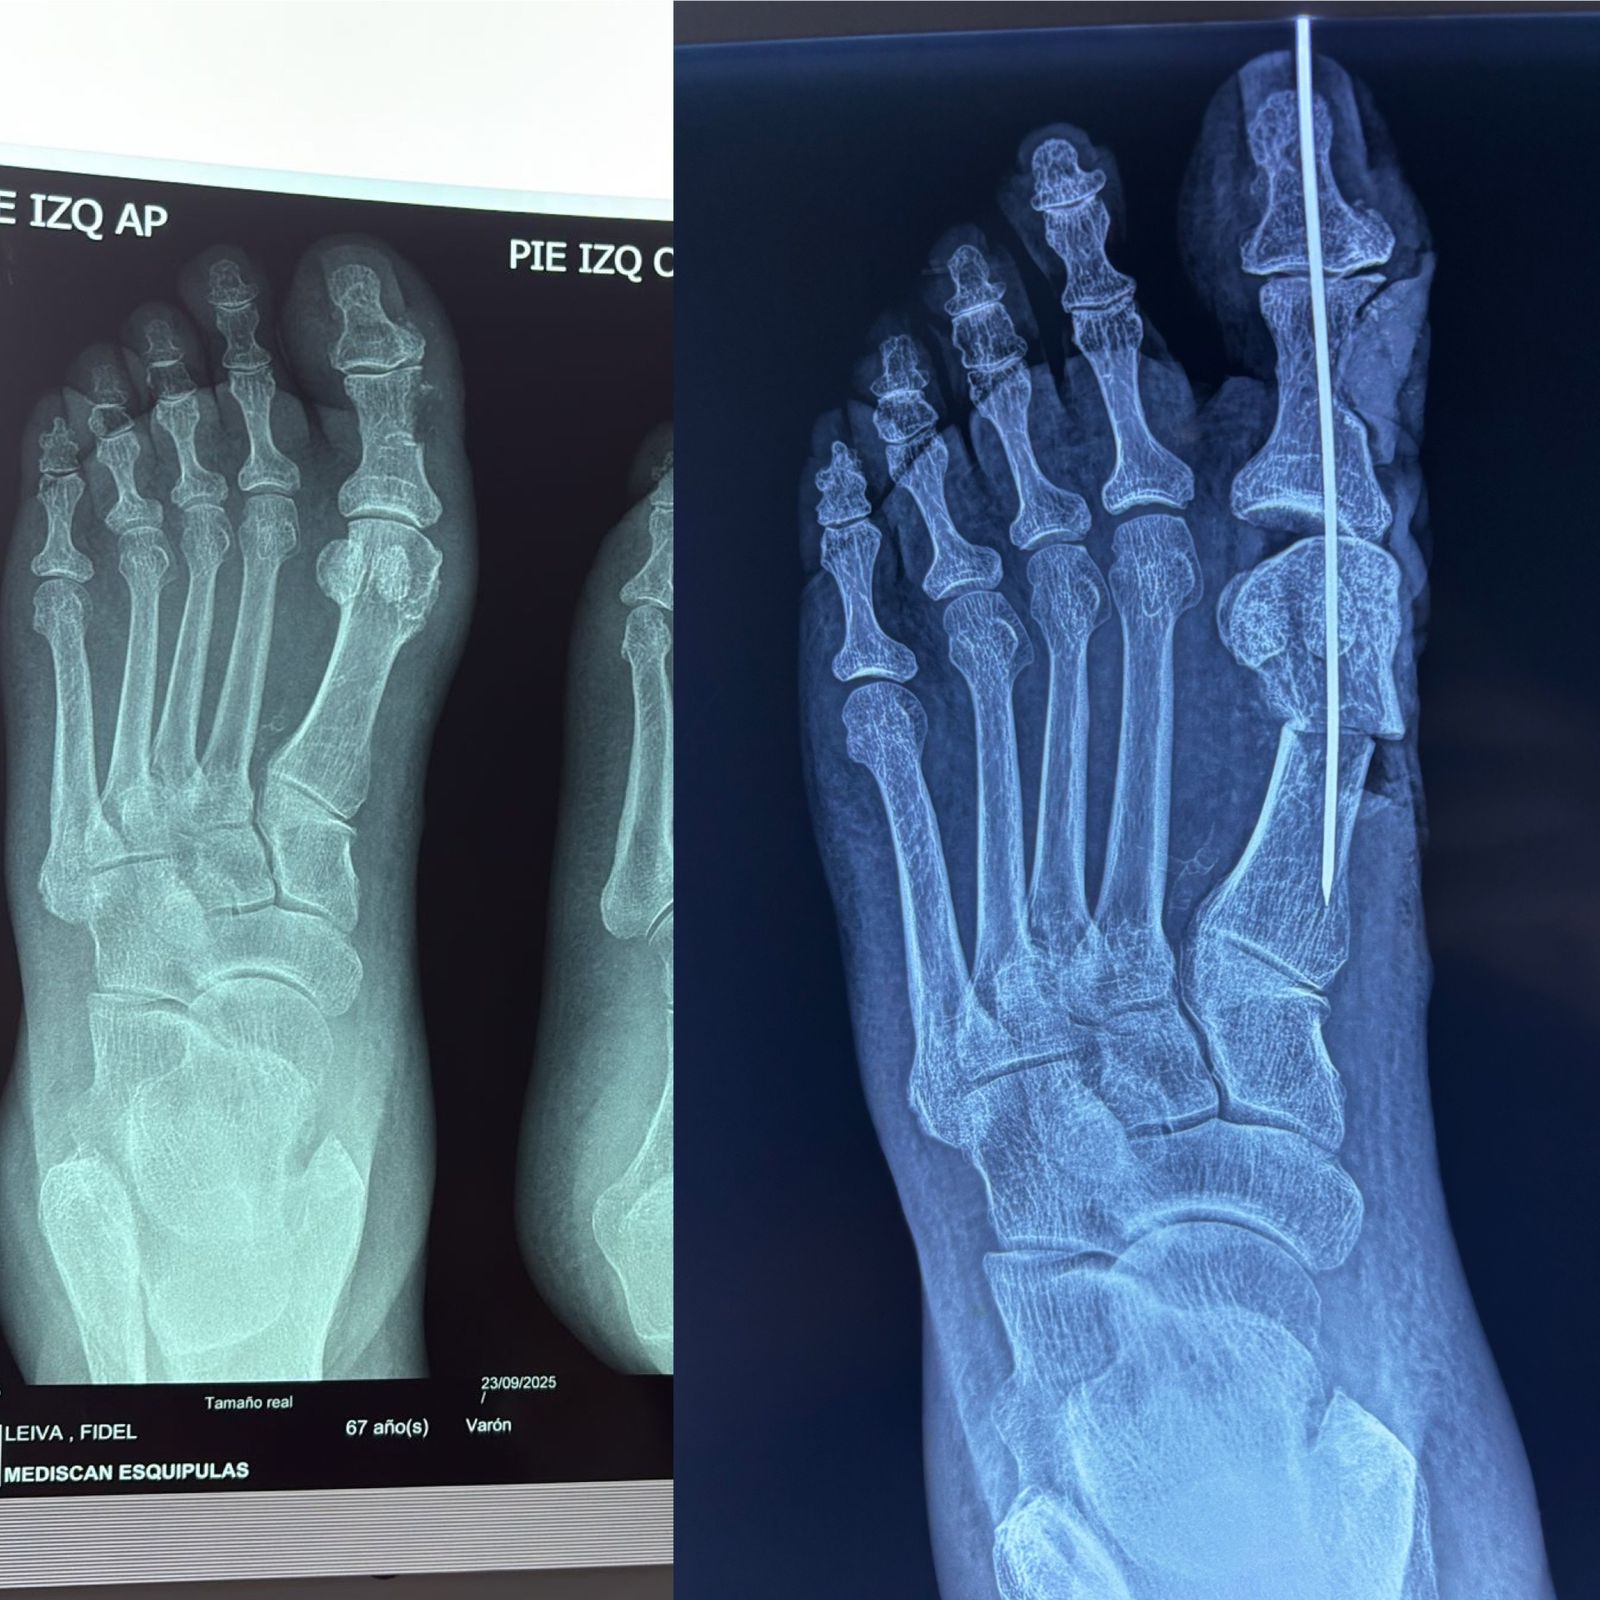

Deformidades digitales y hallux valgus

Artroscopía y cirugía mínimamente invasiva